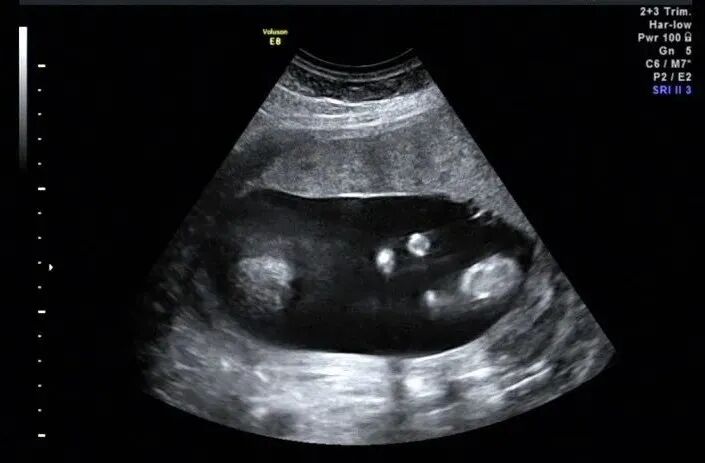

12周后胎儿四肢就可以完整显示,NT筛查时也建议对胎儿四肢进行观察。对于肢体检查最好采用连续追踪扫查法,尽量一次完成,如果由于体位原因看了一半,没有完成,最好在下次观察肢体时依然采用连续不间断扫查把整个肢体检查完毕。扫查时包括关节、肢体姿势、骨骼及皮肤。扫查到手脚后旋转探头打到远端指骨(趾骨)末端,观察手指(脚趾)个数、形态,有无手指(脚趾)缺失、多指(趾)或重叠指等,具体方法如下图

手指个数,这个切面有时大拇指跟其余四指不在同一切面,最好再旋转或移动探头看下大拇指情况

打到足底水平长轴切面后旋转探头显示五个脚趾头,同时足底长轴切面一定要留图。